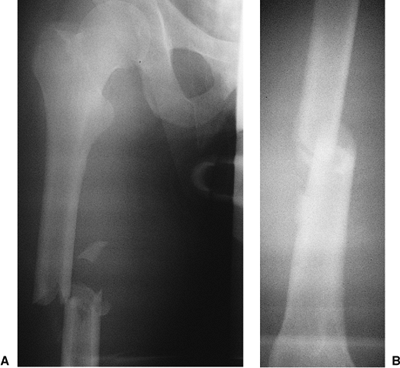

trauma should be evaluated for other injuries. Trauma evaluation and

resuscitation via a multidisciplinary approach is necessary in patients

with multiple injuries. High-quality, full-length anteroposterior (AP)

and lateral radiographs of the femur should be obtained to evaluate the

fracture (Fig. 21.2). The fracture location and

the degree of comminution should be assessed on plain films.

Ipsilateral fractures of the hip or femoral condyles must be ruled out

before nailing is undertaken. Specific hip or knee films are often

necessary for visualizing these fractures. Unrecognized nondisplaced

fractures in these areas may displace during nailing. Once recognized,

these fractures may be amenable to fixation with percutaneous screws.

![]() |

|

Figure 21.2. AP radiograph of the right femur showing a transverse mid-diaphyseal fracture with minimal comminution.

closed right-femur fracture as a result of a head-on motor vehicle

accident. The patient lost consciousness at the site of the accident

and experienced mild retrograde amnesia. On initial examination, the

physician found an obvious, closed, right, midshaft-femur deformity.

The peripheral pulses were intact, and the neurologic examination

showed no abnormalities. Cervical spine, chest, and pelvic radiographs

were normal. A cranial computed tomography (CT) scan was negative for

fracture or intracranial bleed. AP and lateral radiographs of the femur

showed a mid-diaphyseal transverse fracture (see Fig. 21.2). The patient